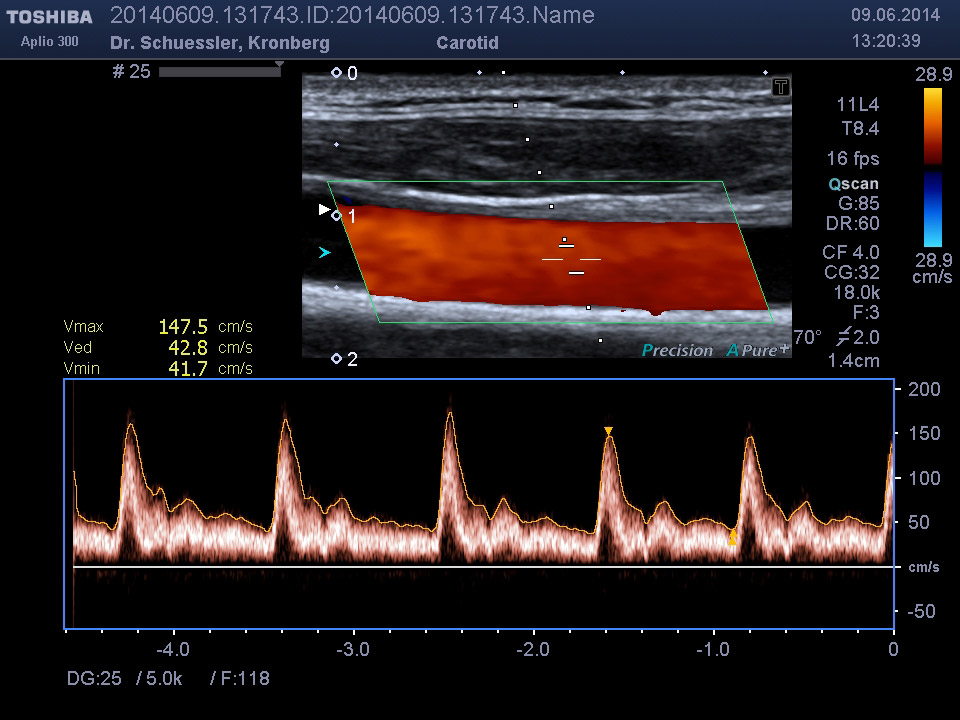

Die farbkodierte Duplexuntersuchung der Gefäße ist ein Ultraschallverfahren und gibt u.a. Auskunft über Verkalkungen, Einengungen, Verschlüsse oder Thrombosen im Bereich der Arterien und Venen.

Die Untersuchung wird angewandt zur Diagnostik von Verengungen in den hirnversorgenden Arterien, Erweiterungen (Aneurysmen) oder Verengungen der Bauchschlagader, Verengungen der Nierenarterien bei Bluthochdruck,  Venenthrombosen und zur Bestimmung des Gefäßrisikoprofils.